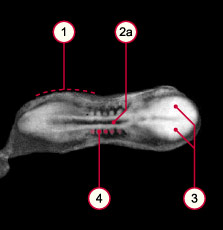

Bonjour, en fait je ne comprends pas pourquoi cette photo est associée au stade carnégie 10, on nous dit que les neuropores sont largement ouverts mais là ils sont fermés

à moins que l'image soit un peu sombre je voudrais avoir votre avis merci Bonne journée

- i1_kyotostad10asml.jpg (8.64 Kio) Vu 643 fois